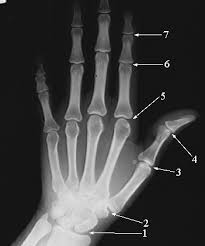

As discoveries progressed, more and more tools became accessible to mankind. Physicians could harness the power of radiation and view into the body without having to perform surgery (X-ray, CAT scan, MRI), chemists could tag enzymes, proteins, and other molecules with radiation to follow reactions within the cell, reactions requiring high amounts of energy could be made, energy could be harnessed from these radioactive reactions, and many other discoveries.